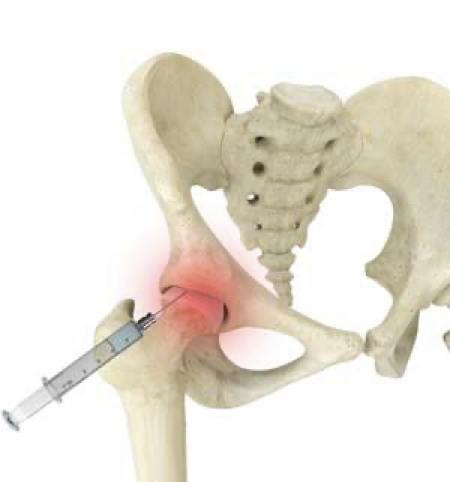

- 注射治疗:皮质类固醇消炎或透明质酸润滑关节。

再生治疗:PRP与干细胞疗法

当保守治疗无效时,再生医学提供创新方案:

1. 富血小板血浆(PRP)疗法

- 原理:从患者血液中提取高浓度血小板,注射至髋关节以释放生长因子,减轻炎症并促进组织修复。

- 优势:微创、恢复快,可能延迟手术需求。

2. 干细胞疗法

- 原理:注射从Umbilical cord Wharton’s jelly ( 脐带华通氏胶)中提取的间充质干细胞,促进软骨再生并调节炎症。

- 优势:可能恢复关节功能并减轻疼痛,常与PRP联合使用以增强效果。

注意:再生疗法虽前景广阔,但非根治手段。疗效因疾病严重程度和患者健康状况而异,通常在其他治疗失败后或作为综合方案的一部分使用。